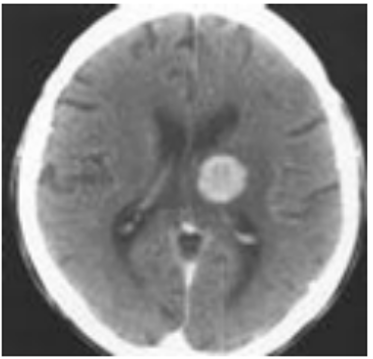

Extensive studies are being conducted to determine the efficacy of using machine learning techniques in the medical field. Disease recognition from many data sources and modeling human-like behavior or thought processes are its primary focuses. Medical data that may be utilized to assist choices in the field of medicine has been routinely collected and stored thanks to recent advancements in computers and innovations in technology. But initially, digital patient data collection and organization is required in most nations. After data collection, diagnostics, signal/image analysis, prediction, and treatment planning are required to arrive at a medical conclusion. Artificial Neural Network (ANN) computing and Support Vector Machines (SVM) are two machine learning techniques that have shown effective in tackling problems of this complexity. The paper includes a study of intelligent approaches for medical decision making that intends to explore and illustrate their potential in this setting.